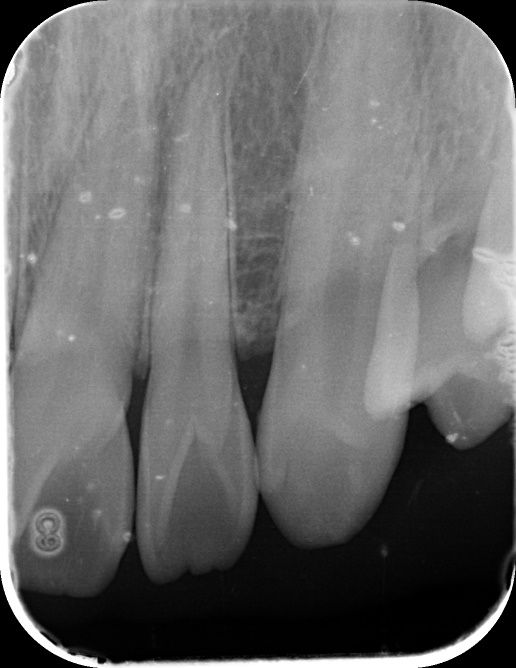

앞니 사이 인접면 충치가 있나요?(사진 첨부)

12, 11, 21, 22 번 4개 앞니 치아들에 대해서

• 2번 째 사진

엑스레이 상으로는 11과 12번의 사이, 21과 22의 사이에 충치가 있는 것으로 보이는데 맞나요?

실제로 바람불어서 긁어봐야 판단이 설 것 같긴한데 일단 엑스레이만 봐서는 관리를 잘한다고 해서 진행을 멈출 사이즈의 충치는 아닌 것 같은데, 지금처럼 인접면 충치의 경우에는 충치부위에 기구접근이 안되기 때문에 딱 충치부분만 제거를 할 수가 없어요. 그래서 좀 더 커질때까지 두고 보자vs지금 치료를 하자 이렇게 나뉜 것 같은데 원래 정석적으로는 바로 치료를 하는게 맞긴 합니다만, 치료를 해서 얻는 것보다 정상치질을 더 제거해야해서 잃는 실이 더 많다고 판단이 되면 좀 더 있다가 하기도 합니다. 이런 애매한 경우는 환자분께서 결정을 하시면 될 것 같습니다.

1. 법랑질 수준에 국한된 충치입니다.

2. 심미적으로 해당 부위가 검게 보이지 않는다면 관리를 하면서 지켜볼 수도 있습니다. 다만 겉으로 보기에는 검게 보인다면 치료를 하는 것이 맞으며 이는 심미적인 이유 때문입니다.

3. 11, 21 모두 치아에 일부 충치가 보입니다. 따라서 2곳 모두 치료해야할 것으로 보입니다.

엑스레이 상으로는 충치가 크게 보이진 않습니다. 저정도라면 저도 일단은 관리를 잘하시면서 지켜보라고 할것같습니다.

사진으로 보기에는 초기 우식이 보이기는 합니다. 하지만 ㅣㅊ료여부는 육안으로 확인을 해야알수가 있어요.

사진응 앞뒤가 겹쳐진 2차원 모잉야지만 충치는 3차원 공간으로 분석을 해야 하기 때문이에요.